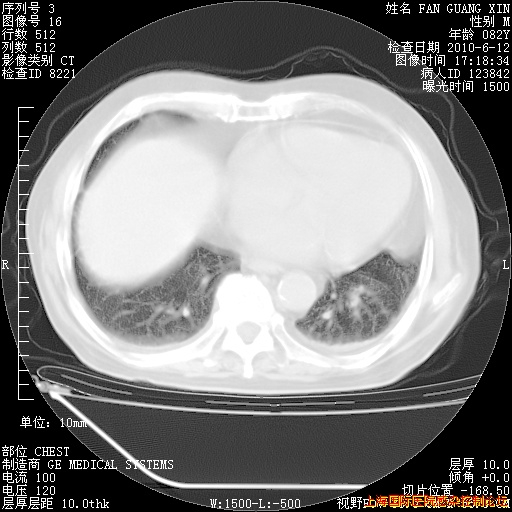

6月12日肺窗

整整相隔30天的肺部CT好像有所好转啊。甲强龙减量第3天,需要观察体温。